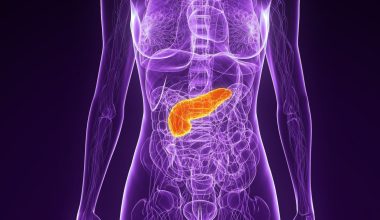

Αν και ο καρκίνος του παχέος εντέρου παραδοσιακά συνδέεται με ηλικιωμένους, όλο και περισσότερες περιπτώσεις εμφανίζονται σε νέους, λόγω των διατροφικών συνήθειων και του τρόπου ζωής.

Σε παγκόσμιο επίπεδο, ο καρκίνος του παχέος εντέρου είναι η τρίτη συχνότερη αιτία καρκίνου και η δεύτερη συχνότερη αιτία θνησιμότητας, ανεξαρτήτου φύλου.

Σε συνέντευξή του στο SuMédico, ο Δρ. Στεφάν Ζίλι Χερνάντεζ, γαστρεντερικός ογκολόγος, προειδοποίησε για την αύξηση των κρουσμάτων καρκίνου σε νεότερα άτομα, δηλώνοντας ότι «δυστυχώς, βλέπουμε τον καρκίνο του παχέος εντέρου να εντοπίζεται σε μεταγενέστερα στάδια και σε νεότερες ηλικίες». Πρόσθεσε πως έχουν αναφερθεί περιπτώσεις προχωρημένου καρκίνου του παχέος εντέρου ακόμα και σε άτομα ηλικίας 30 ετών ή και νεότερα και ότι αυτές δεν σχετίζονται πάντα με γενετικά ή κληρονομικά σύνδρομα.

Ο αντίκτυπος των συνηθειών του τρόπου ζωής

Σύμφωνα με τον Δρ. Ζίλι, όταν ένας ασθενής εμφανίζει καρκίνο του παχέος εντέρου πριν από την ηλικία των 40 ετών, θεωρείται νεαρή περίπτωση. Σε πολλές από αυτές τις περιπτώσεις, ο καρκίνος δεν σχετίζεται με κληρονομικούς παράγοντες, αλλά είναι σποραδικό και αναπτύσσεται από διάφορους παράγοντες, με έναν από τους κυριότερους τη διατροφή. Ο ογκολόγος εξήγησε ότι η σύγχρονη διατροφή, πλούσια σε επεξεργασμένα και υπερ-επεξεργασμένα τρόφιμα, χαμηλή σε φυτικές ίνες και λαχανικά και πλούσια σε κόκκινο κρέας, ευνοεί την ανάπτυξη της νόσου.

«Δεν είναι κακό να τρώμε κόκκινο κρέας, αλλά είναι υγιεινό να τρώμε μία ή δύο φορές την εβδομάδα. Ωστόσο, στις ημέρες μας πολλοί το τρώνε σχεδόν κάθε μέρα» δήλωσε ο Δρ. Ζίλι.

Ο ειδικός συνιστά να ακολουθείτε μια διατροφή που βασίζεται σε λευκέςπρωτεΐνες, όπως το κοτόπουλο και το ψάρι, συνοδευόμενη από μεγάλη ποικιλία φρούτων και λαχανικών, και να διατηρείτε επαρκή ενυδάτωση με φυσικό νερό. Ανέφερε επίσης και άλλους παράγοντες που επηρεάζουν την πρώιμη ανάπτυξη του καρκίνου του παχέος εντέρου:

- Το αλκοόλ

- Το κάπνισμα

- Ο καθιστικός τρόπος ζωής

- Το υψηλό στρες και άγχος

Ο ογκολόγος επεσήμανε ότι αν στους παράγοντες αυτούς προστεθεί και η γενετική προδιάθεση, αυξάνεται η πιθανότητα εμφάνισης καρκίνου του παχέος εντέρου και του ορθού σε νεαρή ηλικία.

Καθυστερημένη διάγνωση του καρκίνου του παχέος εντέρου: Ένα σοβαρό πρόβλημα

Η διάγνωση του καρκίνου του παχέος εντέρου σε πρώιμα στάδια παραμένει μία πρόκληση. Ο Δρ. Ζίλι ανέφερε ότι «τουλάχιστον το 40% όλων των καρκίνων του παχέος εντέρου διαγιγνώσκονται σε προχωρημένο μεταστατικό στάδιο» που σημαίνει ότι ο όγκος έχει ήδη εξαπλωθεί σε άλλα όργανα. Αυτή η καθυστέρηση στη διάγνωση συμβαίνει επειδή τα συμπτώματα συχνά υποτιμώνται, ιδίως στους νέους που πιστεύουν ότι ο καρκίνος του παχέος εντέρου είναι μόνο μια ασθένεια των ηλικιωμένων.

Ο ογκολόγος τόνισε ότι πρέπει να είμαστε σε επιφυλακή για συμπτώματα που θα μπορούσαν να υποδηλώνουν πρόβλημα στο παχύ έντερο, όπως:

- Επίμονος κοιλιακός πόνος

- Παρατεταμένες περίοδοι δυσκοιλιότητας ή διάρροιας.

«Όλοι έχουμε βιώσει αυτή την ενόχληση και την υποτιμούμε, ελπίζοντας ότι θα περάσει σε λίγες μέρες, αλλά αν αυτό δεν συμβεί και τα συμπτώματα επιμένουν, σημαίνει ότι δεν πρόκειται για μια παροδική λοίμωξη και ότι πρέπει να επισκεφθούμε έναν γιατρό» δήλωσε ο Δρ. Ζίλι.

Συνήθως, οι ασθενείς πηγαίνουν στο γιατρό μόνο όταν παρουσιάζουν ανεξήγητη απώλεια βάρους ή όταν βρίσκουν αίμα στις κενώσεις τους. «Τότε είναι που αρχίζουμε πραγματικά να πανικοβαλλόμαστε, αλλά μέχρι να εμφανιστούν αυτά τα συμπτώματα, η νόσος είναι συνήθως προχωρημένη, οπότε είναι σημαντικό να επισκεφτούμε έναν γιατρό μόλις παρατηρήσουμε πόνο που δεν υποχωρεί σε δύο ή τρεις ημέρες, καθώς και ξαφνικές αλλαγές στις κινήσεις του εντέρου μας», συνέστησε.